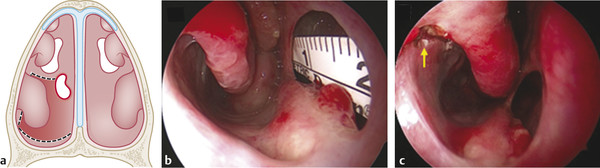

Start measuring the size of the NSP to set the extension of the flap. To improve exposure, it can be useful to outfracture the inferior turbinate (Fig. 17‑2a).

Avoid mucosal tearing during harvesting of the flap. Verify that the flap is pedunculated at the caudal part of the septal mucosa to guarantee the blood supply (Fig. 17‑3).

Rotation and elevation of the flap. Verify the full coverage of the perforation with safety margins (at least 3 mm) to avoid septal reperforation in case of retraction of the flap. (Fig. 17‑3, Fig. 17‑4).